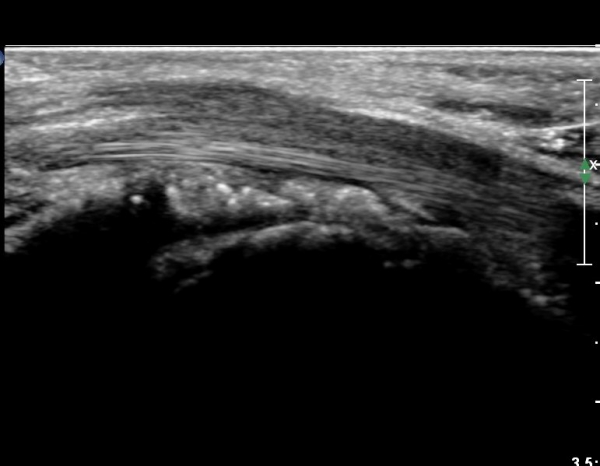

¼Õ¸ñ ºÎÀ§ Ⱦ´Ü¸é°Ë»ç¿¡¼ ¿ä°ñ°ú ¿ù»ó°ñ Àü¹æ¿¡ ¼®È¸È¼º À½¿µÀÌ Á¸ÀçÇϰí Àü¹ÝÀûÀÎ ¼öÁö ±¼°î°ÇÀÇ ºñÈÄ, Á¤Á߽ŰæÀÇ ºÎÁ¾°ú

ÈûÁÙ ¹× Á¤Á߽ŰæÀÇ Ç¥ÃþÀ¸·Î ÀüÀ§°¡ °üÂûµÈ´Ù, (»çÁø 1 ), ÆÄ¿öµµÇ÷¯°Ë»ç¿¡¼ Ç÷·ùÁõ°¡°¡ °üÂûµÊ´Ù(»çÁø 2)..